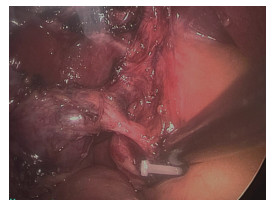

• 患者女,33岁,已婚,因“阵发性右上腹隐痛近1年”于2023年8月12日入院。患者自11个月前,无明显诱因出现右上腹隐痛不适,伴腰背部牵涉痛,其间在当地医院门诊行腹部超声检查提示胆囊结石伴胆囊炎,口服消炎利胆片半个月,症状无明显改善。患者无发热、黄疸,无恶心呕吐,无进行性消瘦和纳差等。既往身体健康,否认乙肝病史,否认其他慢性疾病史,否认传染病史。配偶身体健康。患者直系亲属3代内没有传染性及遗传性疾病史。入院查体:营养良好,体温正常,皮肤、巩膜未见黄染,心肺听诊无异常;触诊腹部柔软,无腹肌紧张、局限性压痛和反跳痛,墨菲征阴性,无肝区叩痛。腹部超声检查示胆囊炎、胆囊结石,胆囊内胆泥淤积;脂肪肝。胰、脾、双肾、双侧输尿管未见异常。磁共振胰胆管造影(magnetic resonance cholangiopancreatography,MRCP)提示胆囊结石、胆囊炎;胆汁浓缩,右肝小囊肿(图 1)。血生化检查示总胆红素17.14 μmol/L,丙氨酸转氨酶14 U/L。

图  1  术前MRCP影像

胆囊壶腹部结石嵌顿,胆囊管高位汇入胆总管.MRCP:磁共振胰胆管造影.

• 图  1   术前MRCP影像